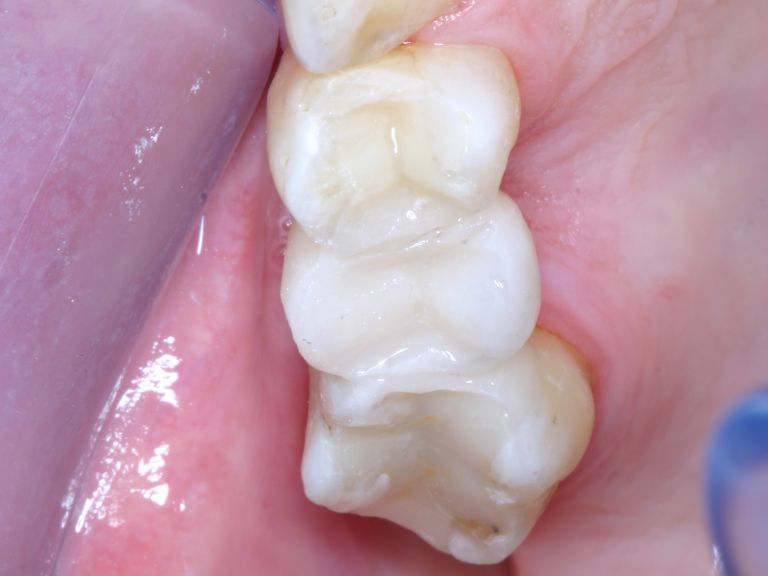

Best Material For Posterior Bridge . No matter how long the bridge you need in the posterior region, solid zirconia can be a great choice. It is very durable and looks great. The choices were limited with cost to. Gordon christensen gives a review of the different types of dental restorative materials on the market and discusses the clinical strengths and weaknesses of each regarding their usefulness as material for posterior crowns. The results of this study support the evidence that zirconia is an appropriate material for anterior and posterior bridges. To help demystify the world of crown and bridge material selection, let's explore the most popular options along with their respective strengths and weaknesses. Zirconia ht is made from a stronger material than that of pfm restorations but still has a natural translucency and excellent esthetics. There were instances of less than ideal. Porcelain, zirconia, or ceramic bridges are popular. Most parameters were rated “a” at all visits. Discuss with your dentist the best materials to ensure a natural appearance and optimal comfort.

Best Material For Posterior Bridge Discuss with your dentist the best materials to ensure a natural appearance and optimal comfort. The choices were limited with cost to. There were instances of less than ideal. The results of this study support the evidence that zirconia is an appropriate material for anterior and posterior bridges. No matter how long the bridge you need in the posterior region, solid zirconia can be a great choice. Zirconia ht is made from a stronger material than that of pfm restorations but still has a natural translucency and excellent esthetics. Most parameters were rated “a” at all visits. To help demystify the world of crown and bridge material selection, let's explore the most popular options along with their respective strengths and weaknesses. It is very durable and looks great. Discuss with your dentist the best materials to ensure a natural appearance and optimal comfort. Gordon christensen gives a review of the different types of dental restorative materials on the market and discusses the clinical strengths and weaknesses of each regarding their usefulness as material for posterior crowns. Porcelain, zirconia, or ceramic bridges are popular.